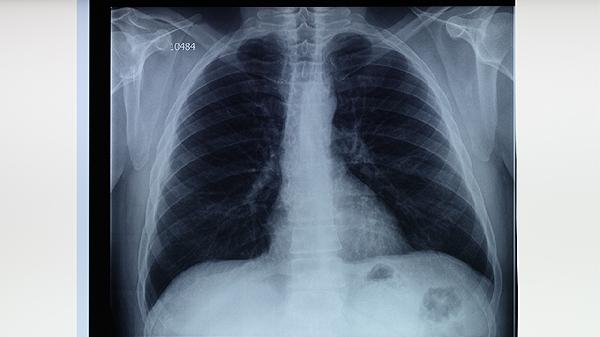

胸部X線檢查是診斷肺結(jié)核的重要影像學(xué)方法,可以顯示肺部病變的位置、范圍和性質(zhì)。肺結(jié)核在X線片上常表現(xiàn)為上肺野的浸潤性陰影、空洞形成或纖維化病灶。胸部X線檢查具有輻射性,孕婦和兒童需謹(jǐn)慎選擇,必要時可采用防護(hù)措施。